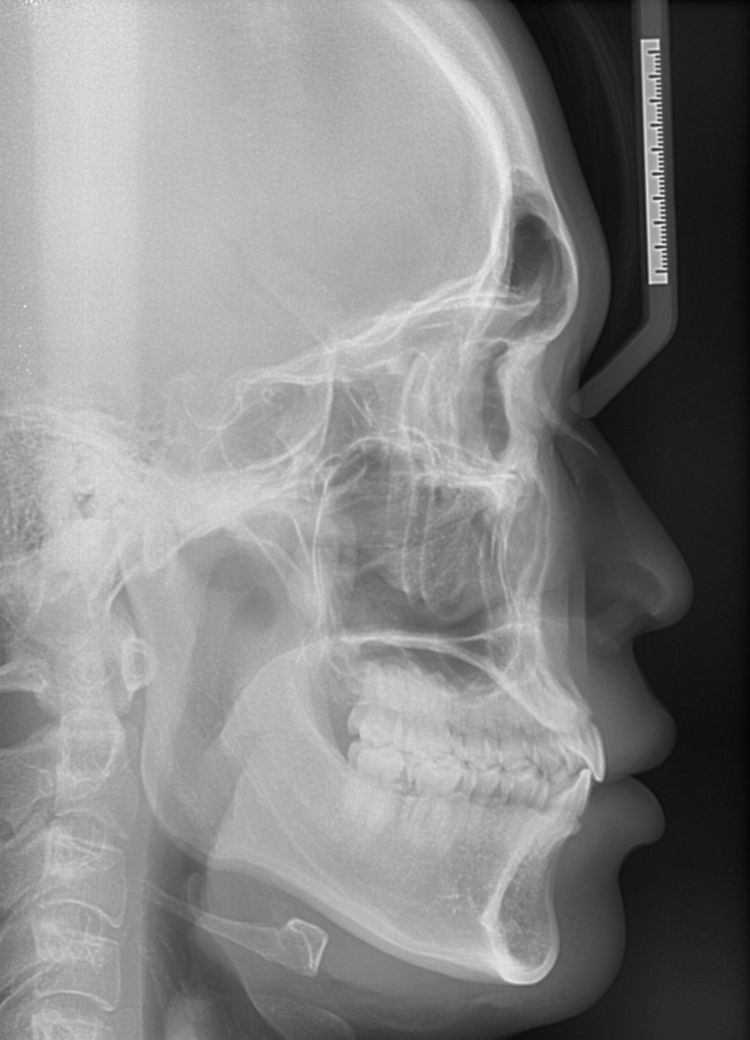

A치과) 상악에 비해 하악이 긴편이나 정상범위라고 볼수 있어 주걱턱은 아니라고 봅니다. 그래서 수술적 치료는 필요치 않아 보입니다. 치아상태는 전치부 총생 및 전방경사가 있고 상악 우측절치 반대교합이 있다 장기적으로는 좋지못하다. 앞니 부분교정 또는 인비절추천

대부분의 경미한 부정교합은 사람마다 있습니다. 치축 경사나 여러가지 상황을 보았을 때 정상범주이며 일부 양쪽 턱관절이 비대칭으로 발생한 턱관절 틀어짐으로 보여집니다. 이 역시 정상범주이며 예민하신 분이 아니라면 살아가는데 크게 불편감이 없어 보입니다. 인비절라인을 하더라도 크게 개선되지 않을 수 있어 보이며 신중하게 하셔야 할 것으로 보입니다.